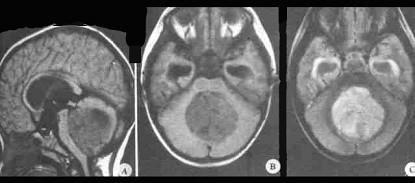

问题 关于髓母细胞瘤(如图所示)哪项正确()

选项 A.来源于胚胎残余组织 B.成人多见,发病高峰在20岁左右 C.发病率无性别差异 D.无播散种植倾向 E.病程较长

答案 A